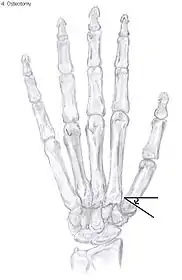

Metacarpal osteotomy

The aim of this procedure is to change the pressure distribution on the CMC1 joint, so it can function without further damaging the joint. That is why a successful osteotomy requires a CMC1 joint of reasonable condition. Therefore, the metacarpal osteotomy should be limited to patients with a stage I-II CMC OA.[39]

An osteotomy is a surgical procedure wherein bone fragments are modified by cutting the bone.

During this procedure an abduction osteotomy of the proximal end of the first metacarpal bone is performed. An incision is made over the radial border of the first metacarpal bone. A wedged shape bone fragment is removed, causing the distal part of the metacarpal bone to tilt towards its desired position.[40] Postoperative, the thumb of the patient is immobilized using a thumb-cast.

Possible complications are non-union of the bone, persistent pain related to unrecognized CMC or pantrapezial disease and radial sensory nerve injury.[39]